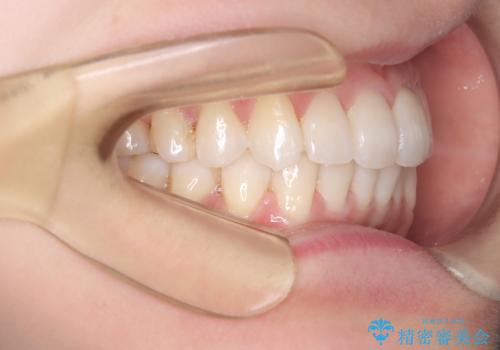

インビザラインモデレートによる前歯の叢生改善|IPR最小限で自然な歯並びへ

- 患者様は、**前歯の叢生(がたつき)**を気にされて来院されました。

できるだけ歯を削らずに、自然な歯並びを手に入れたいというご希望がありました。

診査の結果、中等度の叢生であったため、インビザラインモデレートでの対応が可能と判断しました。

歯へのダメージを抑えるため、IPR(歯間削合)は必要最小限にとどめる方針としました。

前歯の叢生は解消され、自然で調和の取れた歯並びが得られました。

「歯をほとんど削らずにきれいになった」と、患者様にもご満足いただけました。